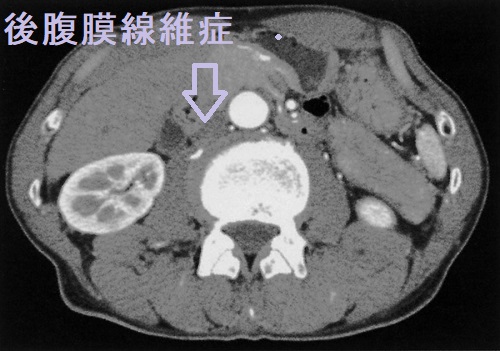

後腹膜線維症では、内臓を包む腹膜の背中側がガチガチに線維化します。腎臓から出て膀胱へ至る尿管を巻き込むため、尿の通過障害が起こります。結果、尿が腎臓へ逆流して、水腎症や急性腎盂腎炎を発症します。[Nephrol Dial Transplant. 2021 Sep 27;36(10):1773-1781.]

CT・MRIでは大動脈周囲に軟部影を認め、炎症性動脈瘤のような所見です。

IgG4 関連疾患との合併から、特発性後腹膜線維症の相当数がIgG4 関連後腹膜線維症とされます。(Intern Emerg Med. 2017 Apr;12(3):287-299.)

後腹膜線維症は

- 橋本病(慢性甲状腺炎)との合併率が高い(Autoimmun Rev. 2015 Jan;14(1):16-22.)

- リーデル甲状腺炎との合併も報告されている(Clin Nucl Med. 2002 Jun;27(6):413-5.)(Pathol Res Pract. 1997;193(8):573-7; discussion 578.)

IgG4 関連後腹膜線維症なら当然と言えます。